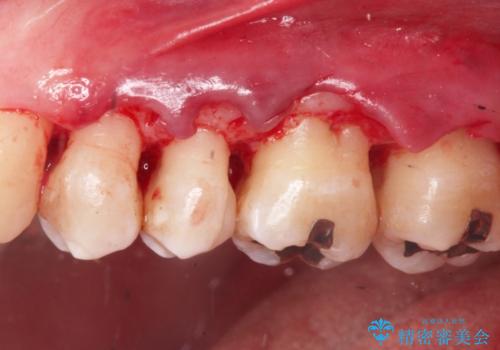

1. 縁下歯石のクリーニングの治療前